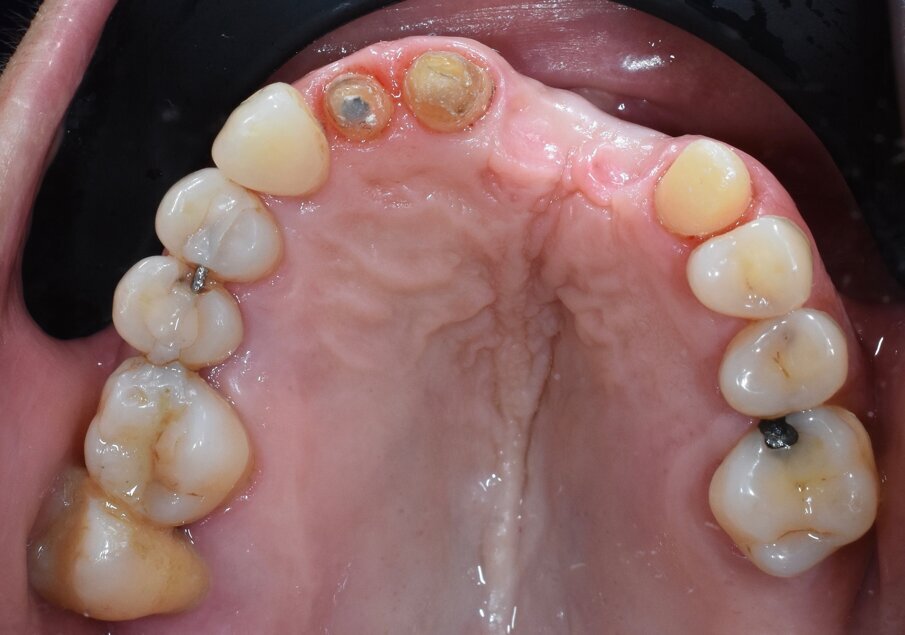

In questo articolo presentiamo un caso clinico che dimostra come il posizionamento improprio di un impianto può rendere impossibile la riabilitazione protesica, che richiede una nuova pianificazione chirurgica e riabilitativa per ottenere l’estetica desiderata. La paziente si presenta alla nostra osservazione con una riabilitazione protesica incongrua, con flangia in resina, a supporto dentale ed implantare, con la presenza di un impianto in posizione 2.1 vestibolarizzato e con l’emergenza nel fornice, in mucosa alveolare. Dalla valutazione della Tac si evince la posizione errata dell’impianto e la perdita consistente in senso trasversale della compagine ossea (Figg. 1, 2). Pertanto si opta per il seguente piano di trattamento che prevede: rimozione dell’impianto e preparazione protesica dell’elemento 2.3, confezionamento di un primo provvisorio a supporto dentale che servirà a guidare la guarigione dei tessuti (Figg. 3-7). A distanza di 4 mesi si procede a un innesto epitelio connettivale libero con prelievo dal palato per compensare il gap dei tessuti molli in senso trasversale, quindi viene ribasato il provvisorio in modo tale da favorire la guarigione dei tessuti (Figg. 8-11). A 9 mesi dalla maturazione dei tessuti si procede alla finalizzazione protesica fissa a supporto dentale (Figg. 12-14).

Fig. 4 - Visione occlusale dopo rimozione del manufatto protesico si noti la posizione errata dell’impianto.